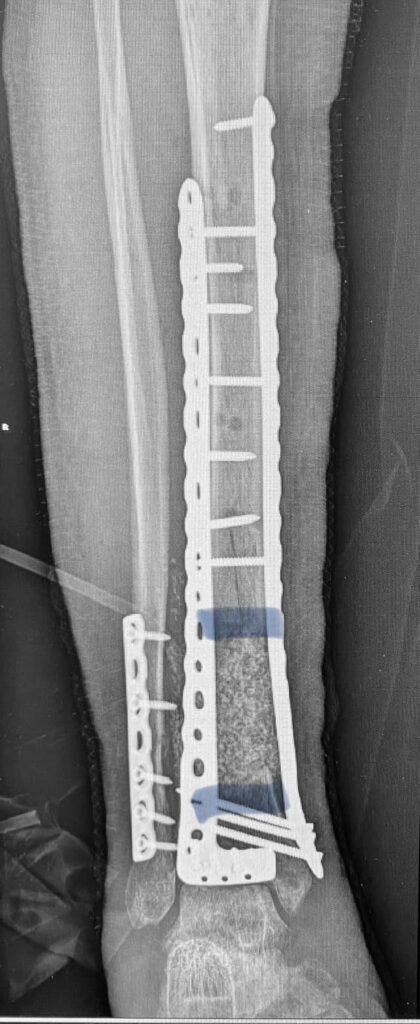

Поэтому следующим этапом мы (доктора Долгош Д.В., Никитин П.В., Парий В.Б. и ваш покорный слуга) взяли 12 см малоберцовой кости (свободный трансплантат) и кортикальную кость из бедра пациента с помощью RIA-2. Как раз этот этап на фото. Черно-белом, чтобы Фейсбук меньше возмущался. Там в фильтре-боксе как раз костная крошка из бедра видна. А она, как вы понимаете, красного цвета . Всё это перемешали еще и с BONALIVE (заменителем кости нового поколения с антибактериальным эффектом) и имплантировали. С ещё одной дополнительной пластиной.